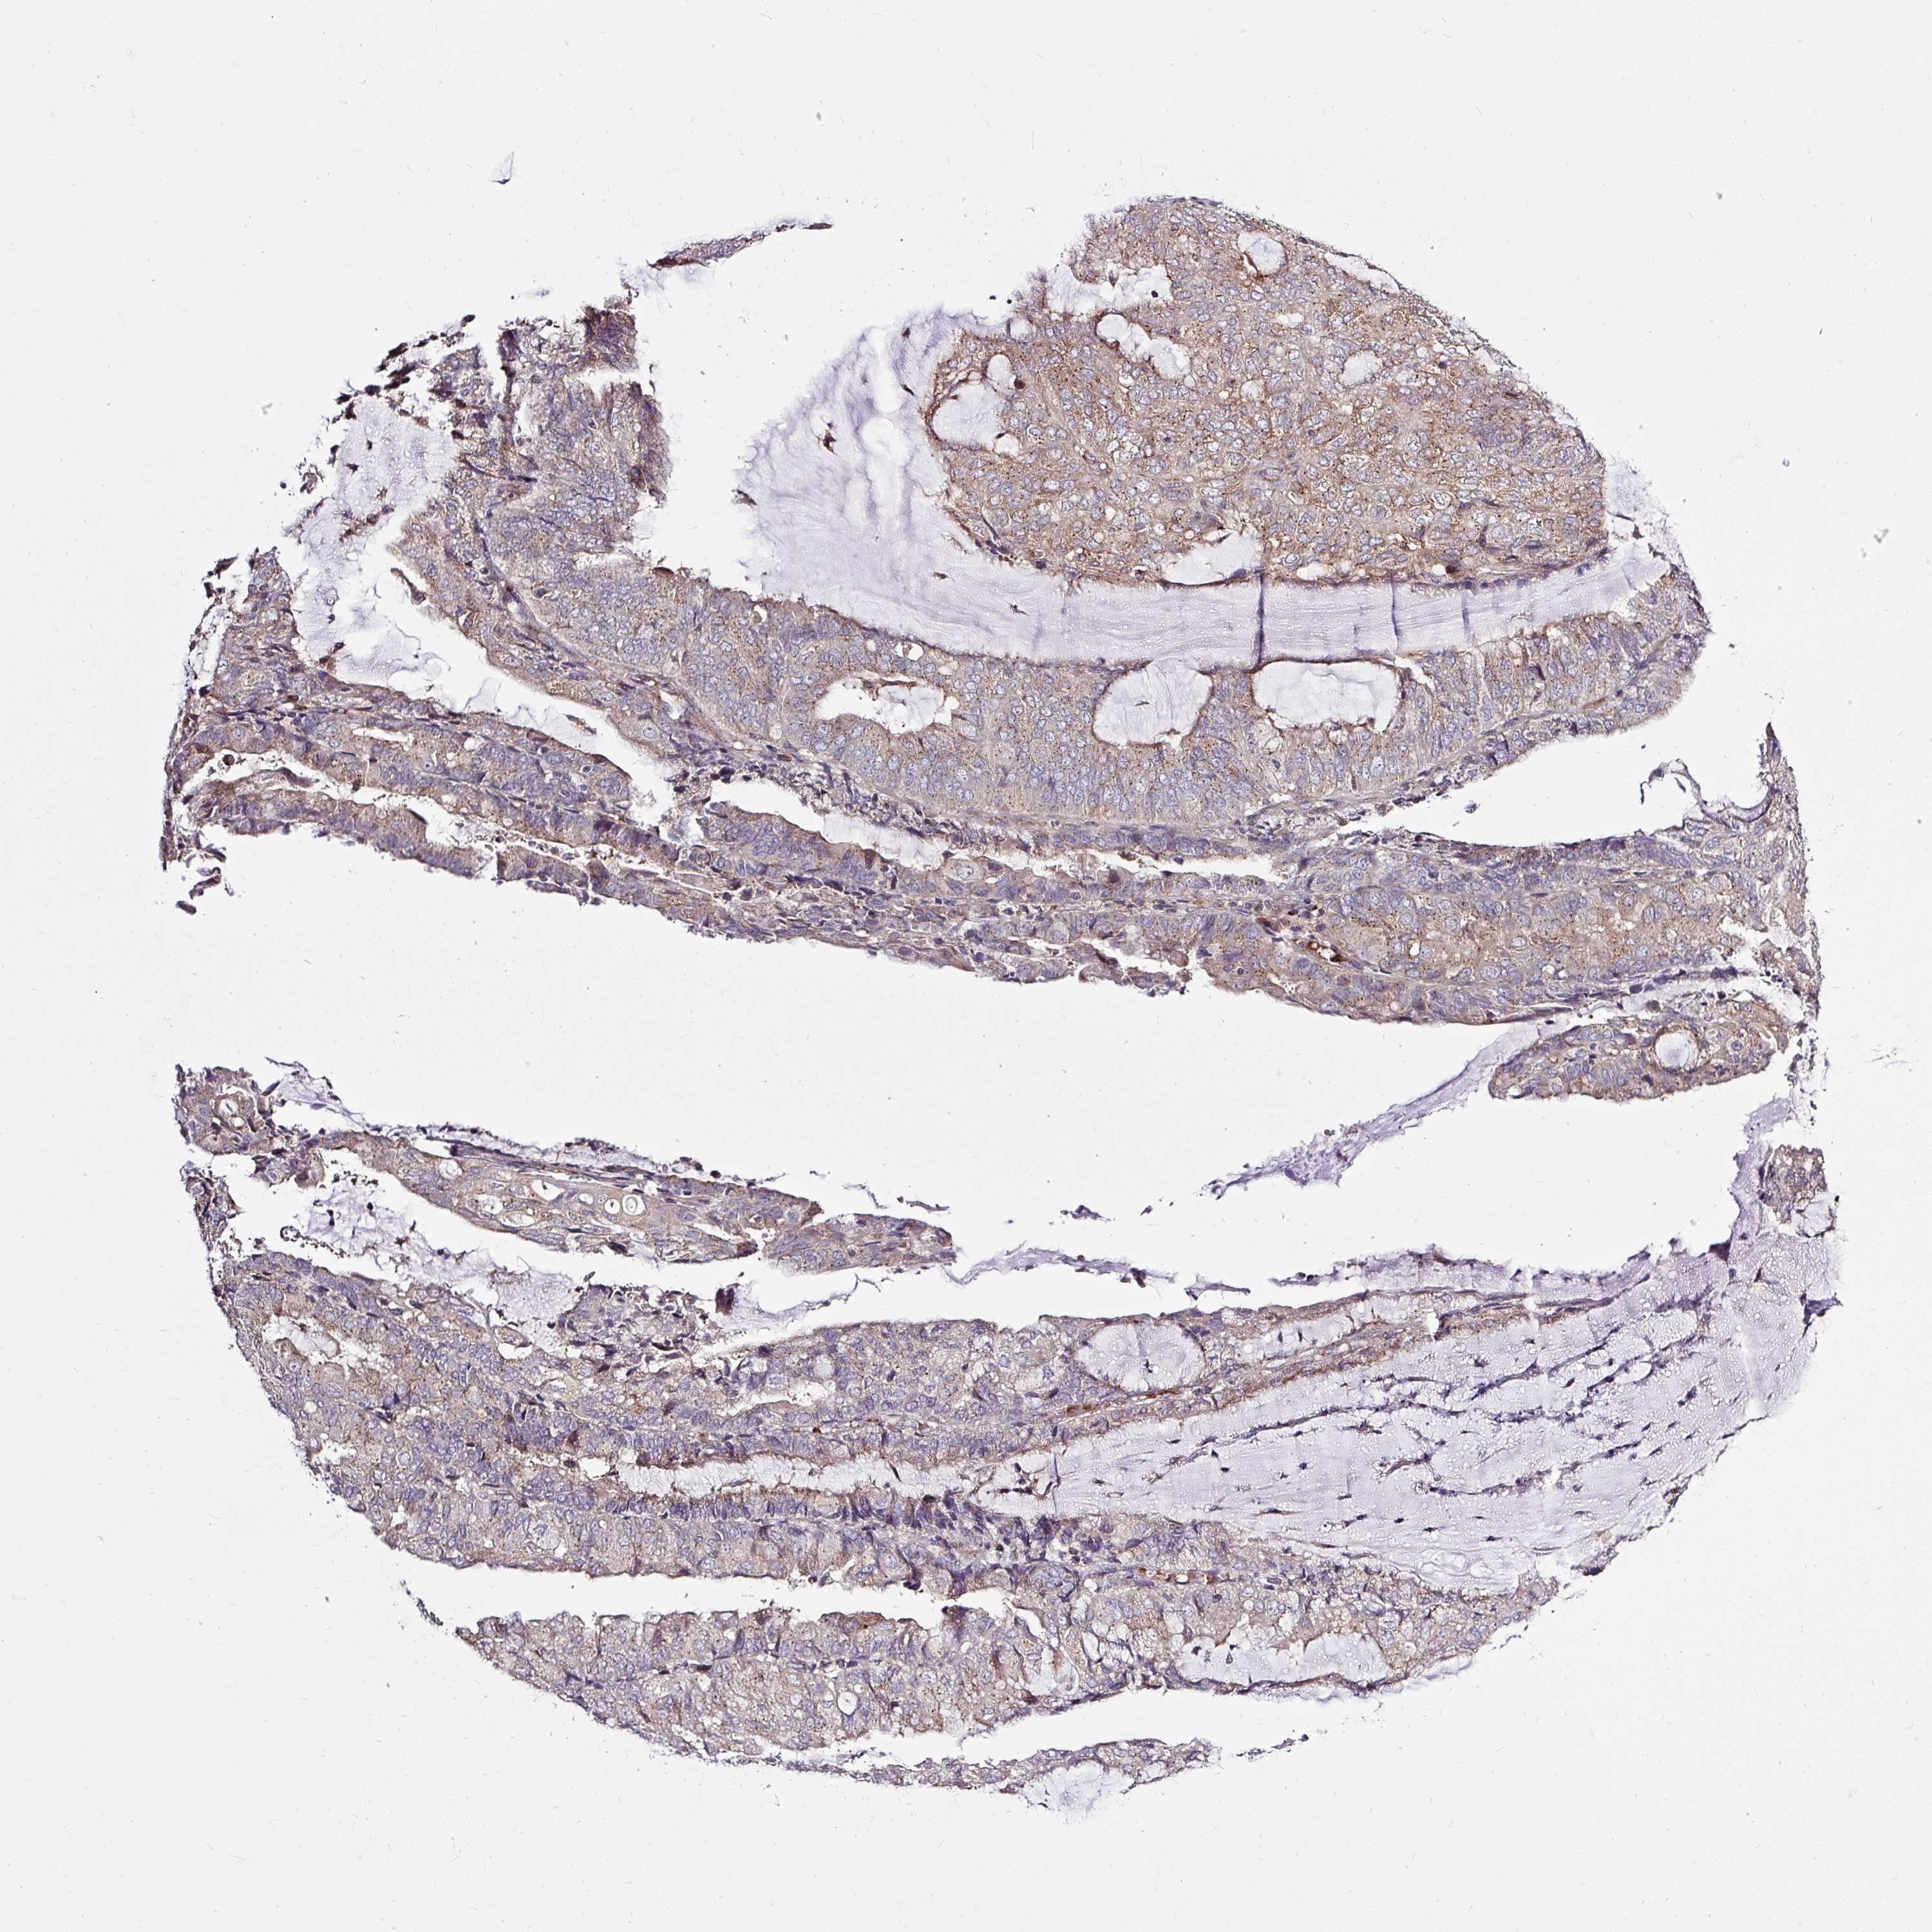

ENDOMETRIAL CANCER - Protein expressioni

A mouse-over function shows sample information and annotation data. Click on an image to view it in a full screen mode. Samples can be filtered based on level of antibody staining by selecting one or several of the following categories: high, medium, low and not detected. The assay and annotation is described here.

Note that samples used for immunohistochemistry by the Human Protein Atlas do not correspond to samples in the TCGA dataset.

Antibody stainingi

Antibody staining in the annotated cell types in the current human tissue is reported as not detected, low, medium, or high, based on conventional immunohistochemistry profiling in selected tissues. This score is based on the combination of the staining intensity and fraction of stained cells.

Each image is clickable and will lead to virtual microscopy that enables deeper exploration of all samples and also displays staining intensity scores, fraction scores and subcellular localization as well as patient and tissue information for each sample.

Antibody HPA029449

Antibody CAB055509

Staining

High

Medium

Low

Not detected

Intensity

Strong

Moderate

Weak

Negative

Quantity

>75%

75%-25%

<25%

None

Location

Nuclear

Cytoplasmic/membranous

Cytoplasmic/membranous,nuclear

Adenocarcinoma, NOS